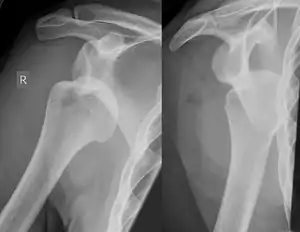

| دررفتگی شانه راست (حفره گودی-کاسهای استخوان کتف خالی است. | |

برحسب جابجایی سر استخوان بازو، در سه حالت دررفتگی به جلو، پشت و پائین اتفاق میافتد، در بیش از ۹۰٪ موارد دررفتگی به جلو* صورت میگیرد.[2]

دررفتگی قدامی

دررفتگی خلفی